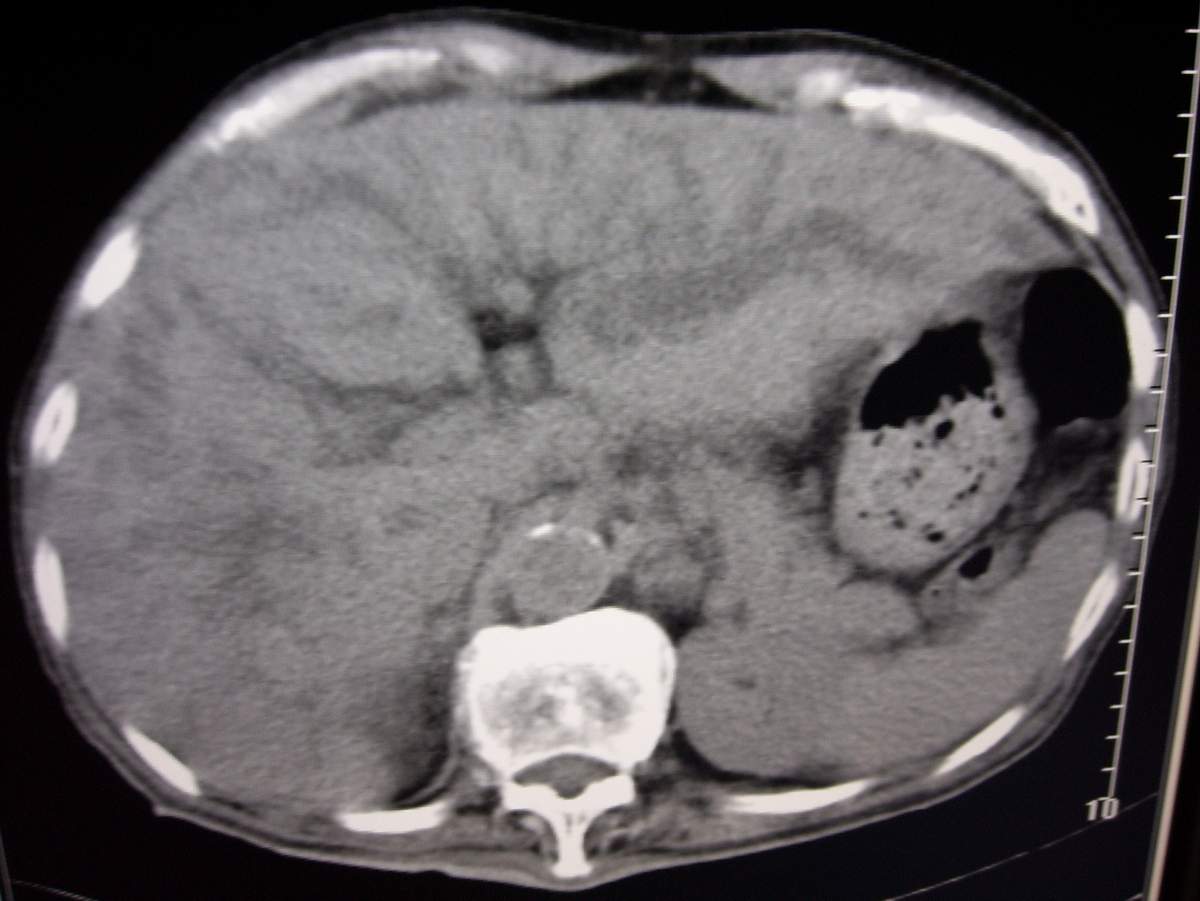

男,77岁,病史不详。

肝内胆管扩张、主胰管扩张 ,胰头影大,考虑胰头癌或胆管下端癌侵犯胰腺可能性大

另外见:胆囊结石 左肾囊肿

慢性胆囊炎,胆结石,左肾囊肿,胰头癌伴肝内胆管、胰管扩张,不除外侵犯肠系膜上静脉的可能。

肝内外胆管明显扩张,肝门区见软组织密度肿块,胆囊壁增厚,胆囊扩大。胰头不大。考虑:肝门区胆管细胞癌。

肝内胆管扩张明显,cbd未见明显扩张,胰管轻度扩张,肝门部胆总管癌?

1肝门区域软组织影,肝内胆管明显扩张,胰管轻度扩张。考虑肝门区胆管细胞癌。2胆囊结石。3左肾小囊肿。

1 肝内外胆管扩张,肝内明显,胰管扩张,胰头明显增大,符合胰头癌双管征。2 胆囊壁略增厚,胆囊内可见高密度结石影,胆囊炎、胆结石3 左肾囊肿